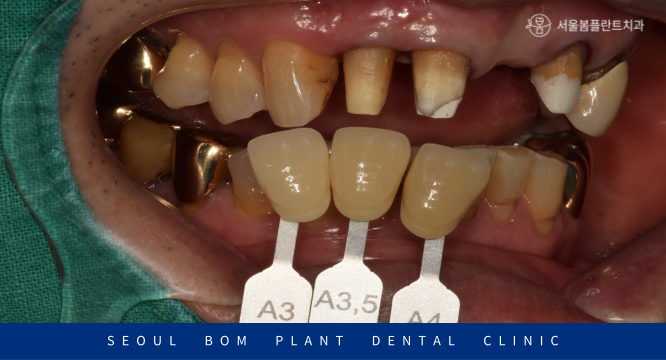

앞니는 다른 사람과 대화를 하거나

웃을 때 눈에 가장 띄는 심미성이 중요한 부위이기 때문에

Shade guide를 이용하여 환자분과 같이 꼼꼼하게

치아 색상을 확인하고 결정하는 과정을 거쳤습니다.